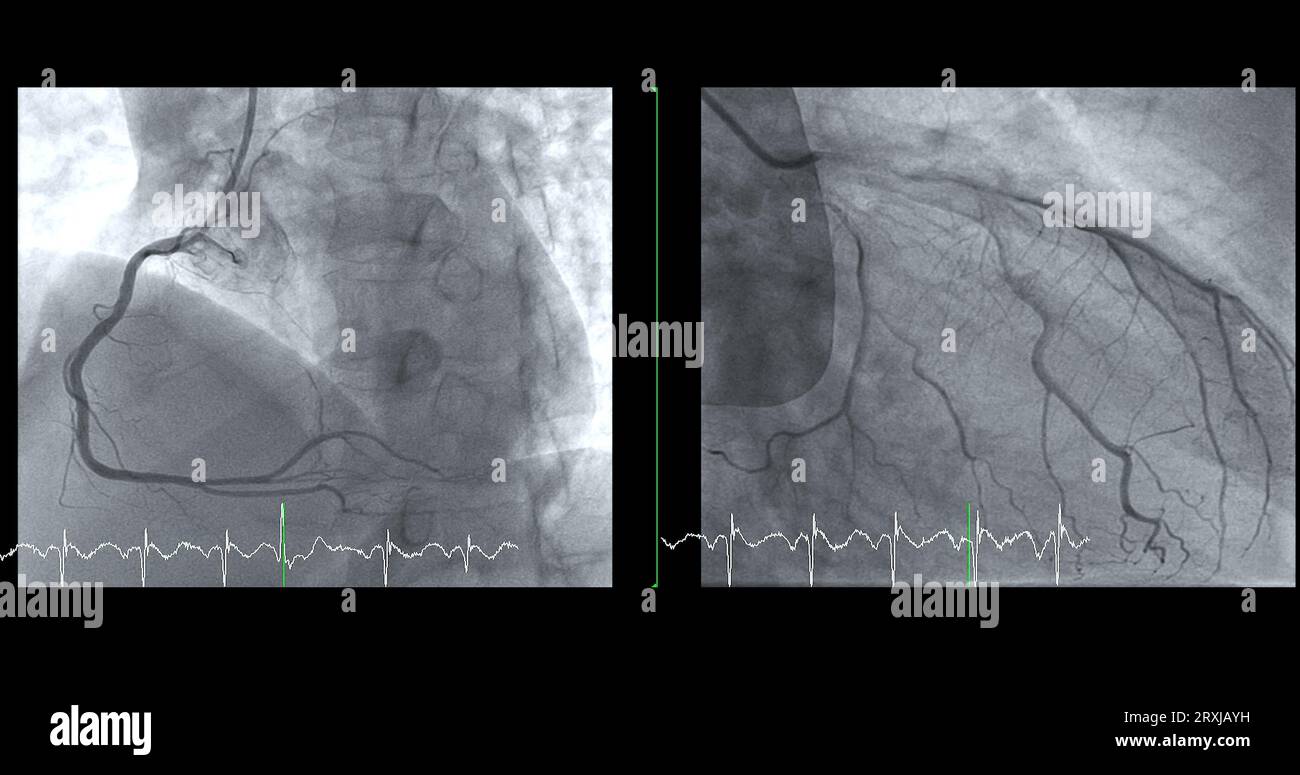

Cardiac catheterization on RCA and LAD can help doctor diagnose and Cardiac Catheterization For Heart Attack For example, your doctor may. Cardiac catheterization (also called cardiac cath, heart cath, or coronary angiogram) is a procedure that allows your doctor to see how. Cardiac catheterization is a common method to diagnose or treat a variety of heart problems. Cardiac catheterization (cardiac cath or heart cath) is a procedure to examine how well your heart is working. A. Cardiac Catheterization For Heart Attack.

Cardiac Catheterization on Left Anterior Descending Artery (LAD Cardiac Catheterization For Heart Attack Cardiac catheterization (cardiac cath or heart cath) is a procedure to examine how well your heart is working. Cardiac catheterization (also called cardiac cath, heart cath, or coronary angiogram) is a procedure that allows your doctor to see how. After a coronary angiogram, depending on the severity and pattern of any blockages detected in the coronary arteries, 3 common treatment. Cardiac Catheterization For Heart Attack.